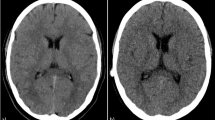

Additionally, SNR and contrast to noise ratio (CNR) were calculated as previously described (depicted in Eqs. 1 and 2)7. Regions of interest (ROI) were placed in the pulmonal trunk at the site of bifurcation, the descending aorta at the same height as the pulmonal trunk and muscle tissue at the same height as the pulmonal trunk. Pectoral muscles were used the background standard for the calculations. Due to the varying age and primary pathologies of the included patients, ROI size was scaled for each patient individually to include as much tissue as was available at the predetermined height as demonstrated in Fig. 1. All series were additionally rated to assess whether they sufficiently answered all clinical questions based on a numeric scale with 0 being non-diagnostic series, 1 some questions were answered, 2 most questions were answered, and 3 all questions were sufficiently answered.

Twenty-seven patients, six female (22%) and 21 male (78%), were retrospectively analyzed. CCT was performed for pre-operative assessment and for the evaluation of potential major aortopulmonary collateral arteries (MAPCAs) in hypoplastic left heart syndrome (HLHS; n = 6, 22%), Tetralogy of Fallot (FOT; n = 5, 19%), pulmonary atresia (n = 5, 19%), total anomalous pulmonary venous return (TAPVR; n = 4, 15%), double outlet right ventricle (DORV; n = 4, 15%), single coronary ostium (n = 1, 4%), transposition of the great arteries (TGA; n = 1, 4%), and aorto-left ventricular tunnel (ALVT; n = 1, 4%). The median age was 109 days (IQR 6–199). The median CTDIvol was 0.34 mGy (IQR 0.22–0.51) while the median DLP was 5.2 mGy*cm (IQR 3.5–7.8). The calculated ED resulted in a median value of 0.21 mSv (IQR 0.14–0.30) after using a tissue specific conversion factor (k) of 0.039 for a pediatric thorax under the age of 0 years calculated from a 32 cm phantom. All performed CCT scans were able to fully answer all clinical questions (3 points on a maximum 3 point-scale with an interclass correlation coefficient of 1.00). Seventy-seven percent of the scans (n = 21) had an image quality score of excellent or good (15 to 12 points) while the lowest score was eight (poor quality, n = 1, 4%). Examples of acquired image quality are provided in Figs. 2, 3, 4, 5.